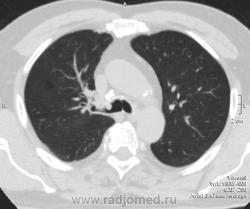

имеющее обсуждение образование одно в области правого главного бронха.. явственно эндобронхиального происхождения.. но что мешает придраться к аксиальным срезам с перитрахеальной ненормальной плотностью?..

Вношу ясность: тут два исследования - первое исследование сделано в понедельник, второе во вторник - в просвете бронха имеет место что то симулирующее tr, что было на верхней стенке, а затем переместилось на нижнюю за сутки - слизь.